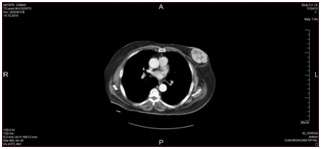

We report a 73-year-old male with UPS . The tumor presented clinically as an enlarging mass in the left breast with a history of one year. There was no history of trauma, nipple discharge, or any other breast lumps. Furthermore, patient had no personal or family history of breast cancer and has never received prior chemotherapy or radiotherapy. The patient had no history of blood transfusion. On physical examination, in the left breast a firm and rounded mass, about 7x7cm diameter, behind the nipple areola complex was palpable. There was no retraction of the overlaying skin and no palpable lymph nodes in the left axillary. Right breast and right axillary were completely normal. Breast ultrasound revealed a solid hypoechoic mass with central necrosiss in the left breast, bilateral axilla were reported as normal. A computer tomography indicated 5x8cm mass with high peripheral vascularity and hypodense necrotic central appearance (Figure 1). In the lower lobes of the left lung, two nodules were observed in the superior and medial basal segments, measuring 7mm and 6mm respectively (Figure 1). There was no pectoral muscle invasion by the mass. Tru-cut biopsy confirmed the pathological diagnosis of UPS and wide excision including nipple areola copmlex was performed (Figure 2). Postoperative course went uneventful. Written informed consent was obtained from the patient. Tissue samples of the primary tumor were taken by the general surgery department. A small piece of the tumor sample and the peripheral blood sample were obtained for genetic study (for FISH and chromosome analysis). The analysises of the FISH and chromosome in cancer and blood samples were performed/done in the genetic laboratory of the Department of Medical Biology and Genetics, Faculty of Medicine, Çukurova University. Standard cytogenetic techniques to detect the blood SCAs were used.

Figure 1 A computed tomography scans of the mass: Normal bilateral axillathe tumor mass in the left breast with high peripheral vascularity and hypodense necrotic center.